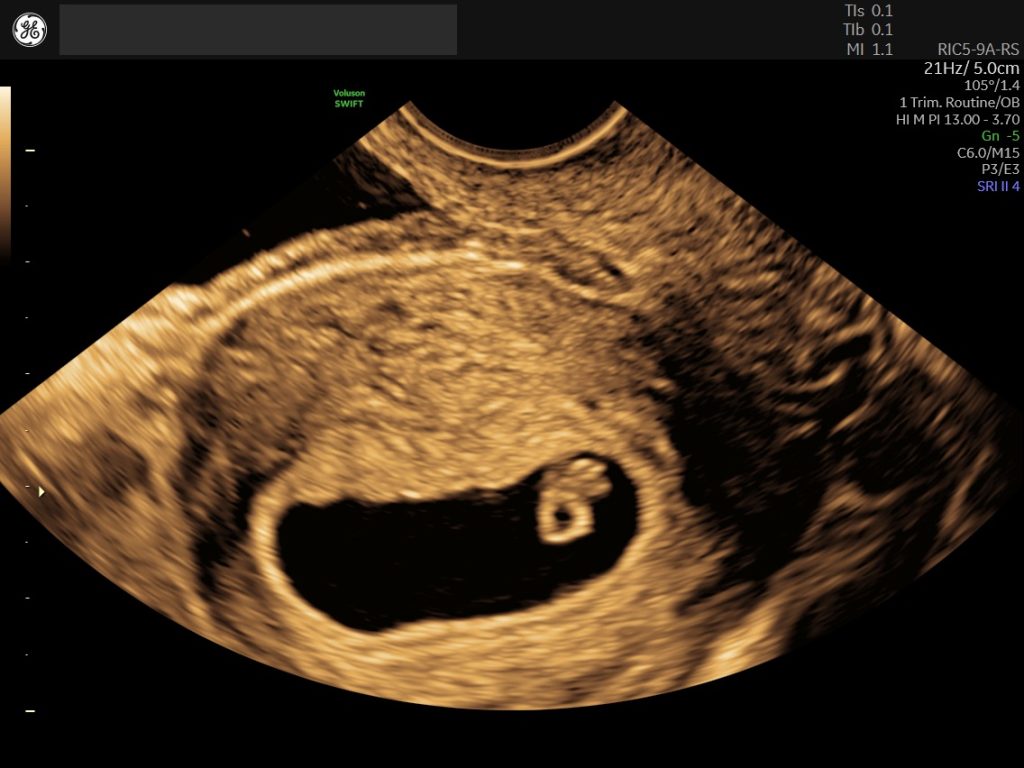

If you’re looking to confirm pregnancy as soon as possible, our early pregnancy is available from just 5 weeks. Recommended if there has been bleeding, pain a history of miscarriage, ectopic pregnancy, IVF treatment or history of long-term medical conditions.

Find out how far along you are with our pregnancy dating scan. By measuring from the first day of your last period, we can determine the fetal gestation age in weeks